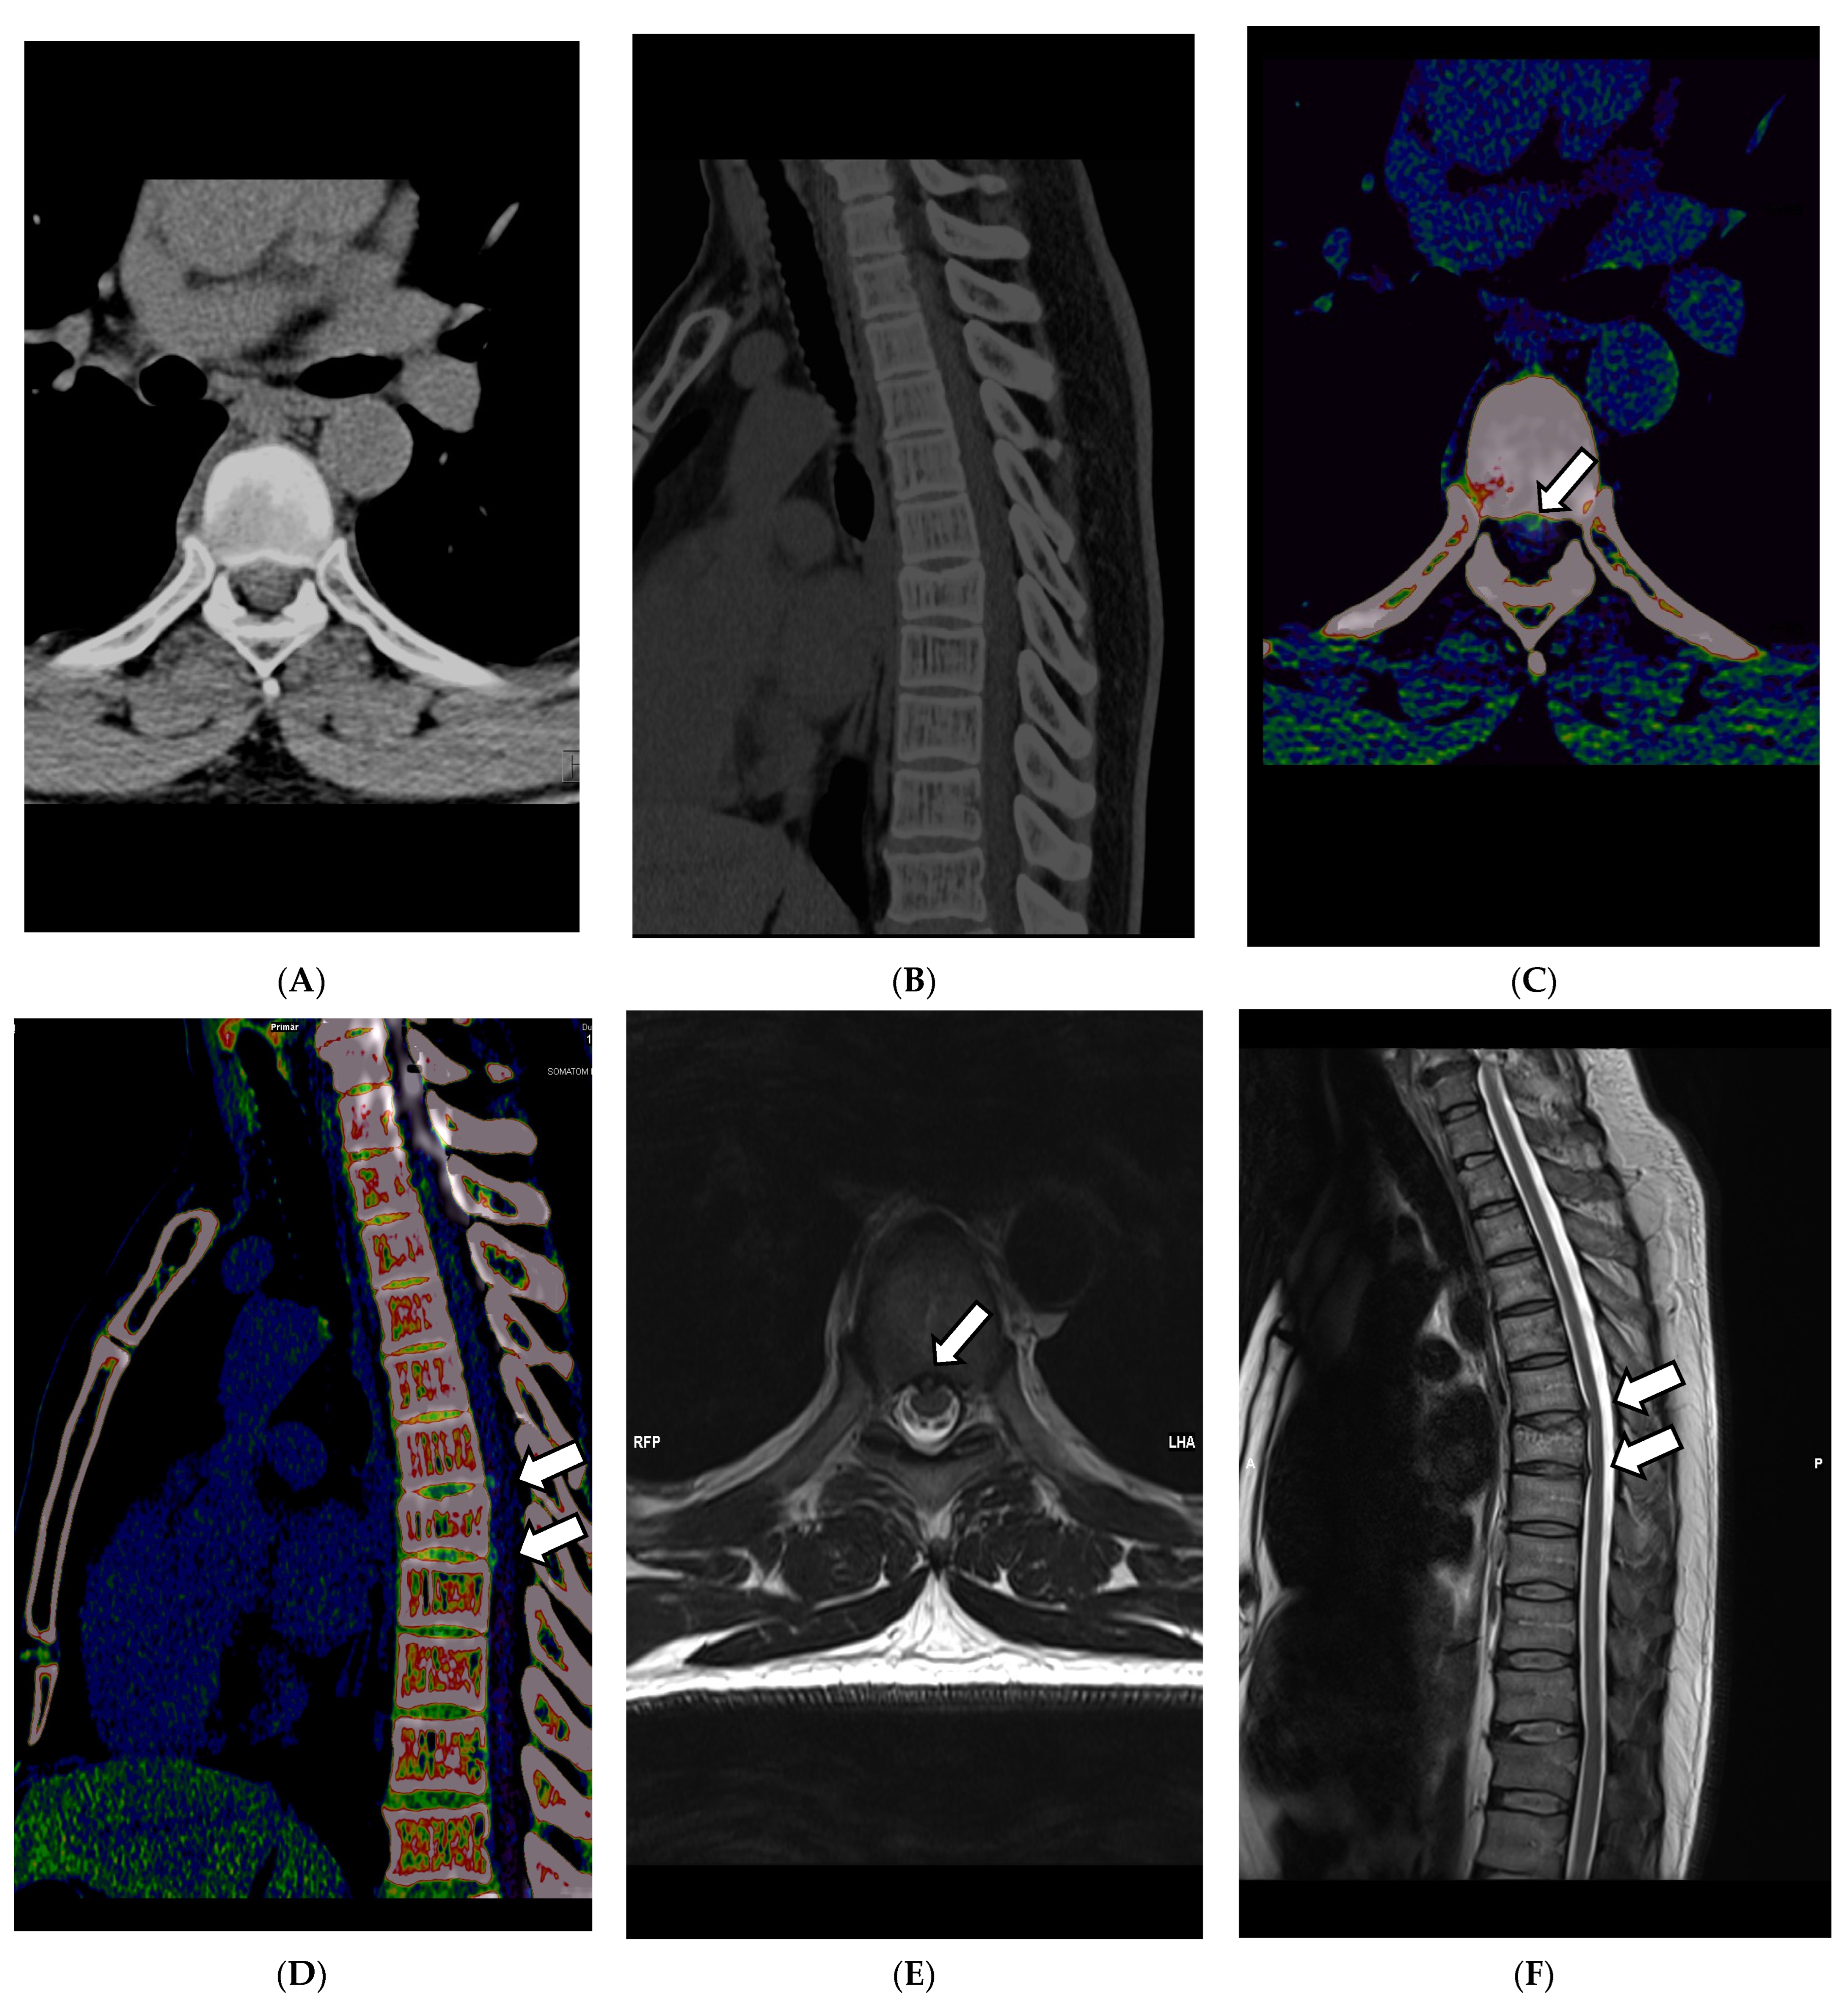

Applications such as color-coded VNCa enable improved visualization of disc herniation (see Figure 4A–D). In 2021, Koch et al. evaluated the diagnostic sensitivity, specificity, and accuracy of color-coded VNCa for the detection of thoracic disc herniation. They found that DECT was significantly better in the tested categories than conventional CT, with a sensitivity of 95% in DECT vs. 73% in SECT and a specificity of 96% in DECT vs. 82% in SECT [64].

Figure 4.

DECT scan of the thoracal spine in a 61-year-old female patient that presented herself with focal pain at the upper back in the clinical examination after slipping and falling on her back. The clinicians suspected a possible vertebral fracture. Thus, a CT scan without a contrast agent was scheduled. During the reading of the images, fractures were ruled out quickly. In the VMI 120 kV soft tissue kernel CT reconstruction, as shown in (A) axial and (B) in sagittal orientation, disk herniation was hardly visible. Application of color-coded VNCa DECT reconstructions finally revealed dorsal median disc herniations (indicated by the white arrows in (D,F)) in segments T 6/7 and T 7/8, as seen in (C) in axial orientation and (D) in sagittal orientation. The finding was later verified in a 1.5 Tesla MRI examination, where the disc herniation could be correlated to the CT findings, as seen in the axial T2-WI sequence (E) and the sagittal T2-WI sequence (F).

Another helpful feature of VNCa is the possibility of detecting bone marrow alterations in trauma CT scans of the spine, as described by Booz et al. in Radiology in 2019 and as described by Fevres et al. in 2022, which are usually not readily visible in conventional CT. After severe trauma to the spine, it is common to use CT acquisition to rule out fractures of the cervical spine, which are barely visible in conventional radiography [45,65,66,67]. By subtraction of calcium from the bone, differences in the bone marrow are depictable, such as hematoma of the vertebral body, in a color-coded overlay, which will be added as an overlay map over the 120 kV anatomical reconstruction of the CT images. This leads to significantly improved detectability of BME with a sensitivity reported by Cavallaro et al. of 89% and a specificity of 98% [45,49,66]. In 2022, Gruenewald et al. reported a very high potential for VNCa as a predictive mean for the volumetric evaluation of bone mineral density (BMD) for the 2-year occurrence risk of osteoporosis-associated fractures, with 85.45% sensitivity and 89.19% specificity [61]. All the recent developments in this field are highly promising for trauma imaging and workflow improvement by enabling a sensitive method for detecting pathologies and gaining information usually only accessible for patients undergoing MRI acquisitions, which are often not accessible in an acute clinical setting. Consequently, DECT facilitates an excellent potential for time and cost savings in departments with limited access and promotes responsible use of diagnostic means and resources.